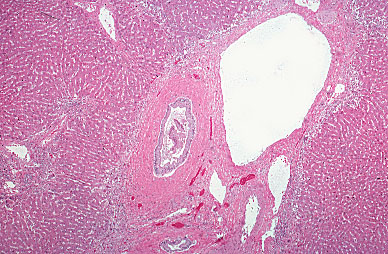

Primary sclerosing cholangitis, histology

There is concentric layering of collagen around larger bile ducts in the liver parenchyma.